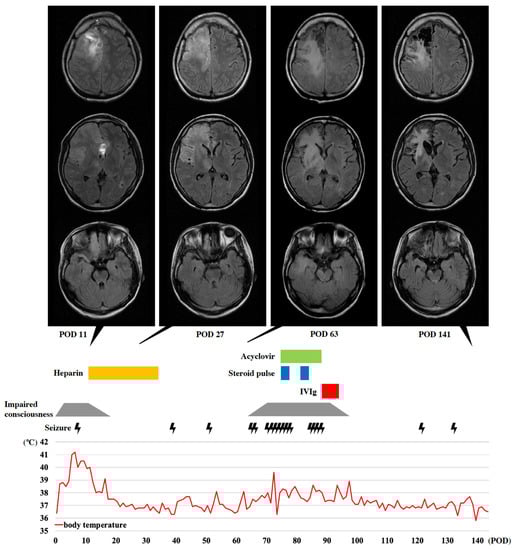

2.2. Progressive Neurological Deficits (Suspected Autoimmune Encephalitis)

2.3. Progressive Neurological Deficits Resolved after Immunotherapy